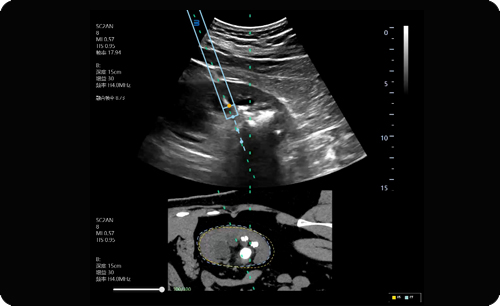

Enhanced needle visualization in 2D, to avoid unintended injury.

For puncturing tissue to establish access.